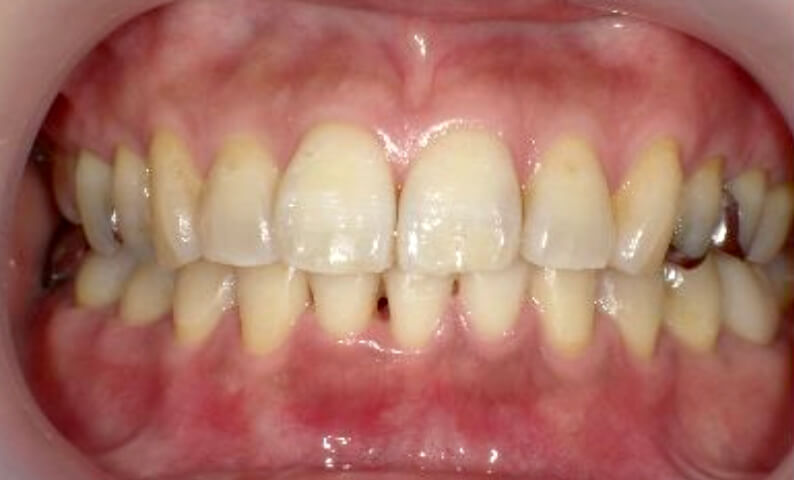

症例_030 上下顎の部分矯正

治療期間:12ヶ月金額:54万円+税女性八の字/V字型捻転歯前歯のガタガタ

| Before | After |

|---|---|

|